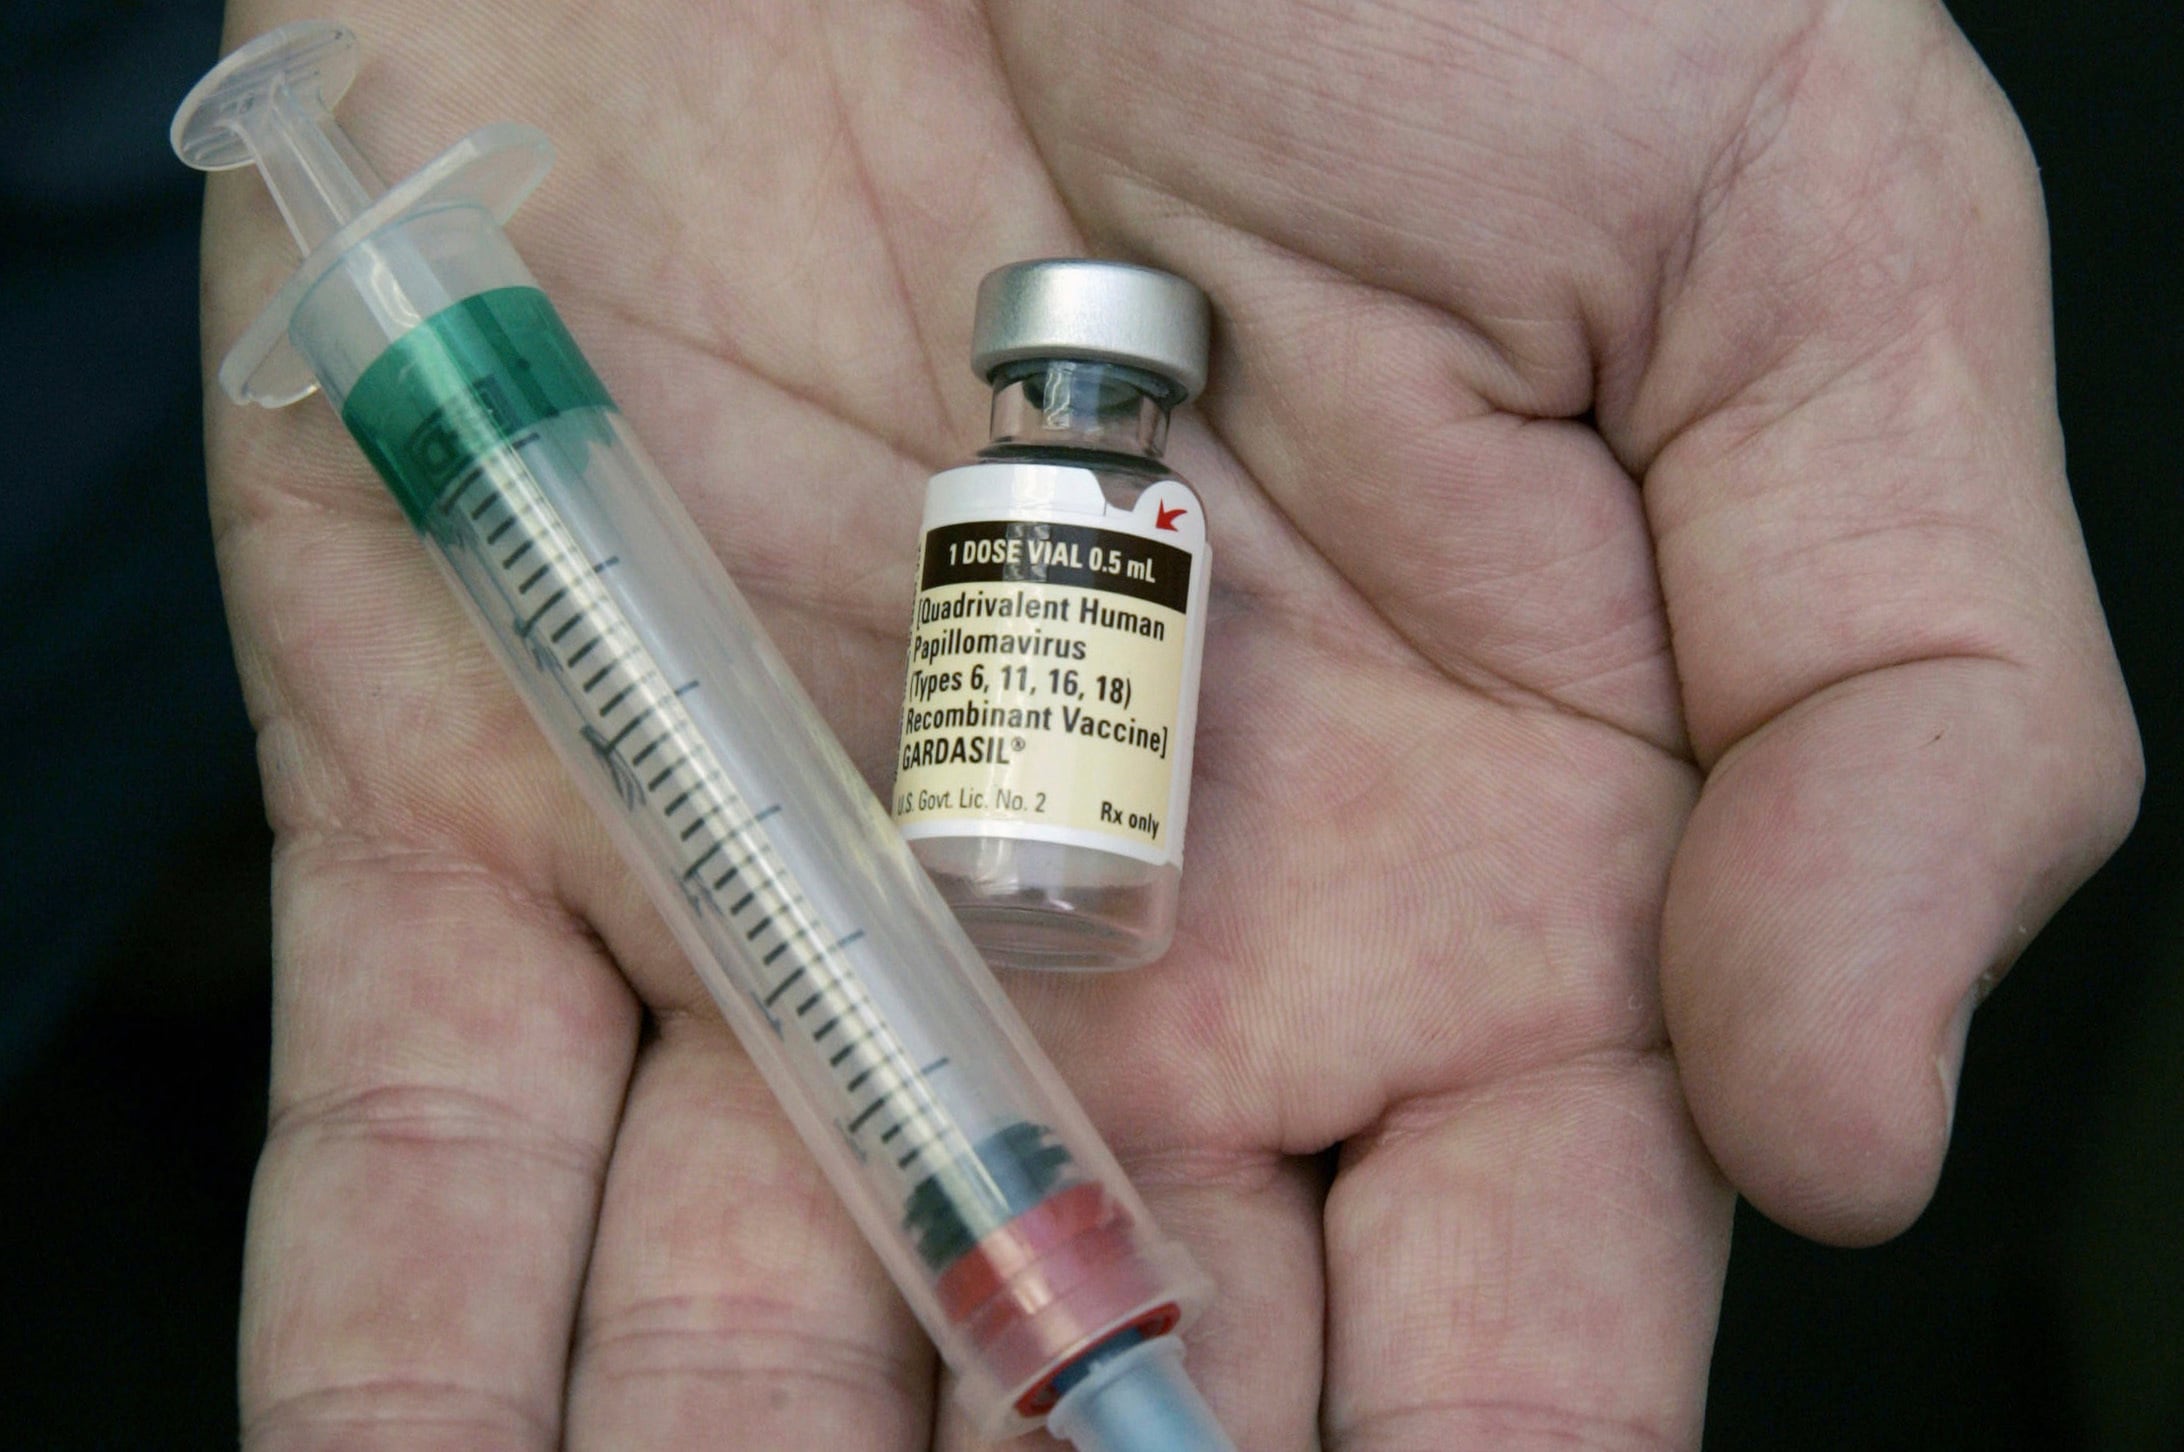

La vacuna contra el VPH, incorporada al Calendario Nacional de Vacunación (CNV), fue un hito en la lucha contra el cáncer de cuello uterino y otras consecuencias graves del virus. La OMS impulsa la estrategia 90-70-90 para la eliminación de esta enfermedad, que propone vacunar al 90% de las niñas antes de los 15 años, garantizar que el 70% de las mujeres accedan a pruebas de detección a los 35 y 45 años, y asegurar que el 90% de las mujeres diagnosticadas con lesiones precancerosas reciban tratamiento.

La recuperación de las coberturas de vacunación es un objetivo central de la política sanitaria. La OMS promueve líneas de acción concretas y el fortalecimiento de la educación en salud para enfrentar la desinformación. La prevención del VPH y otras enfermedades prevenibles requiere no solo el inicio de los esquemas, sino también su cumplimiento en tiempo y forma.

El impacto positivo de la inmunización se refleja en la disminución de la carga de enfermedades y en la posibilidad de erradicar patologías asociadas. Cada dosis aplicada no solo protege al individuo, sino que también reduce la circulación de los agentes infecciosos y contribuye a la salud colectiva.

La evidencia científica respalda la efectividad de las vacunas para evitar complicaciones graves, hospitalizaciones y muertes. La baja cobertura representa una amenaza para los avances logrados en las últimas décadas, y exige una respuesta coordinada entre autoridades, equipos de salud, familias y la comunidad en general.